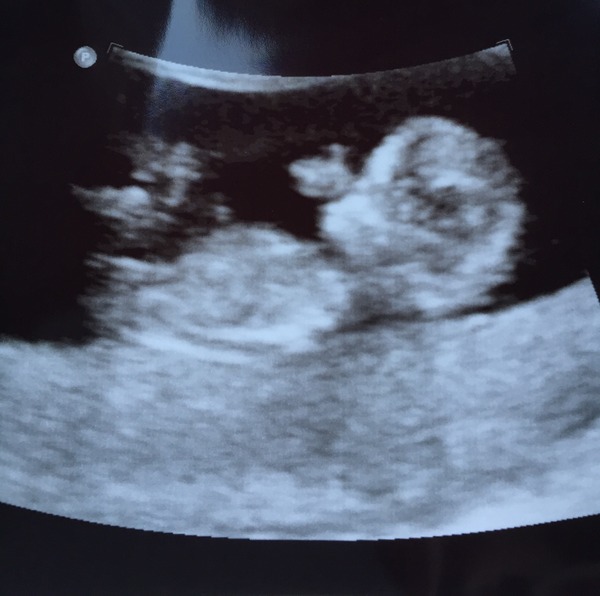

StoneBaby · 06/01/2015 15:11

Jen - congratulations

Had my scan this morning. One healthy heart beat. Very pleased and relieved. Measuring 12 weeks so my EDD has moved up a day.

Here's the little bean.

July 2015 - more and more beans are seen on scans